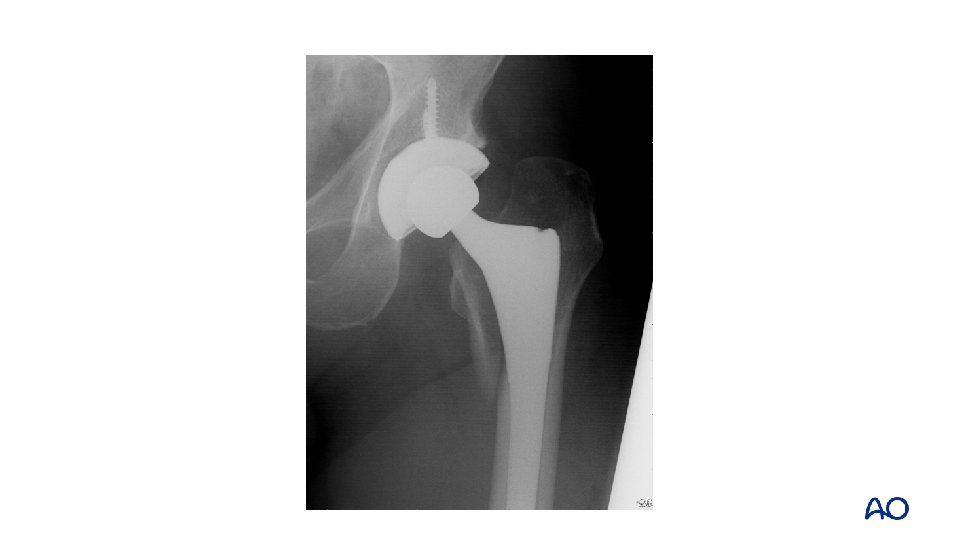

Case 1: Case description • • 78 -year-old Cementless total hip replacement 6 weeks ago Fell at home Severe pain—was unable to get it up

Case 1 • • Describe the implant and the fracture Classify

Case 1 • • Cup is well fixed Stem is loose Fracture extends into greater trochanter (B 2) Distal diaphysis intact